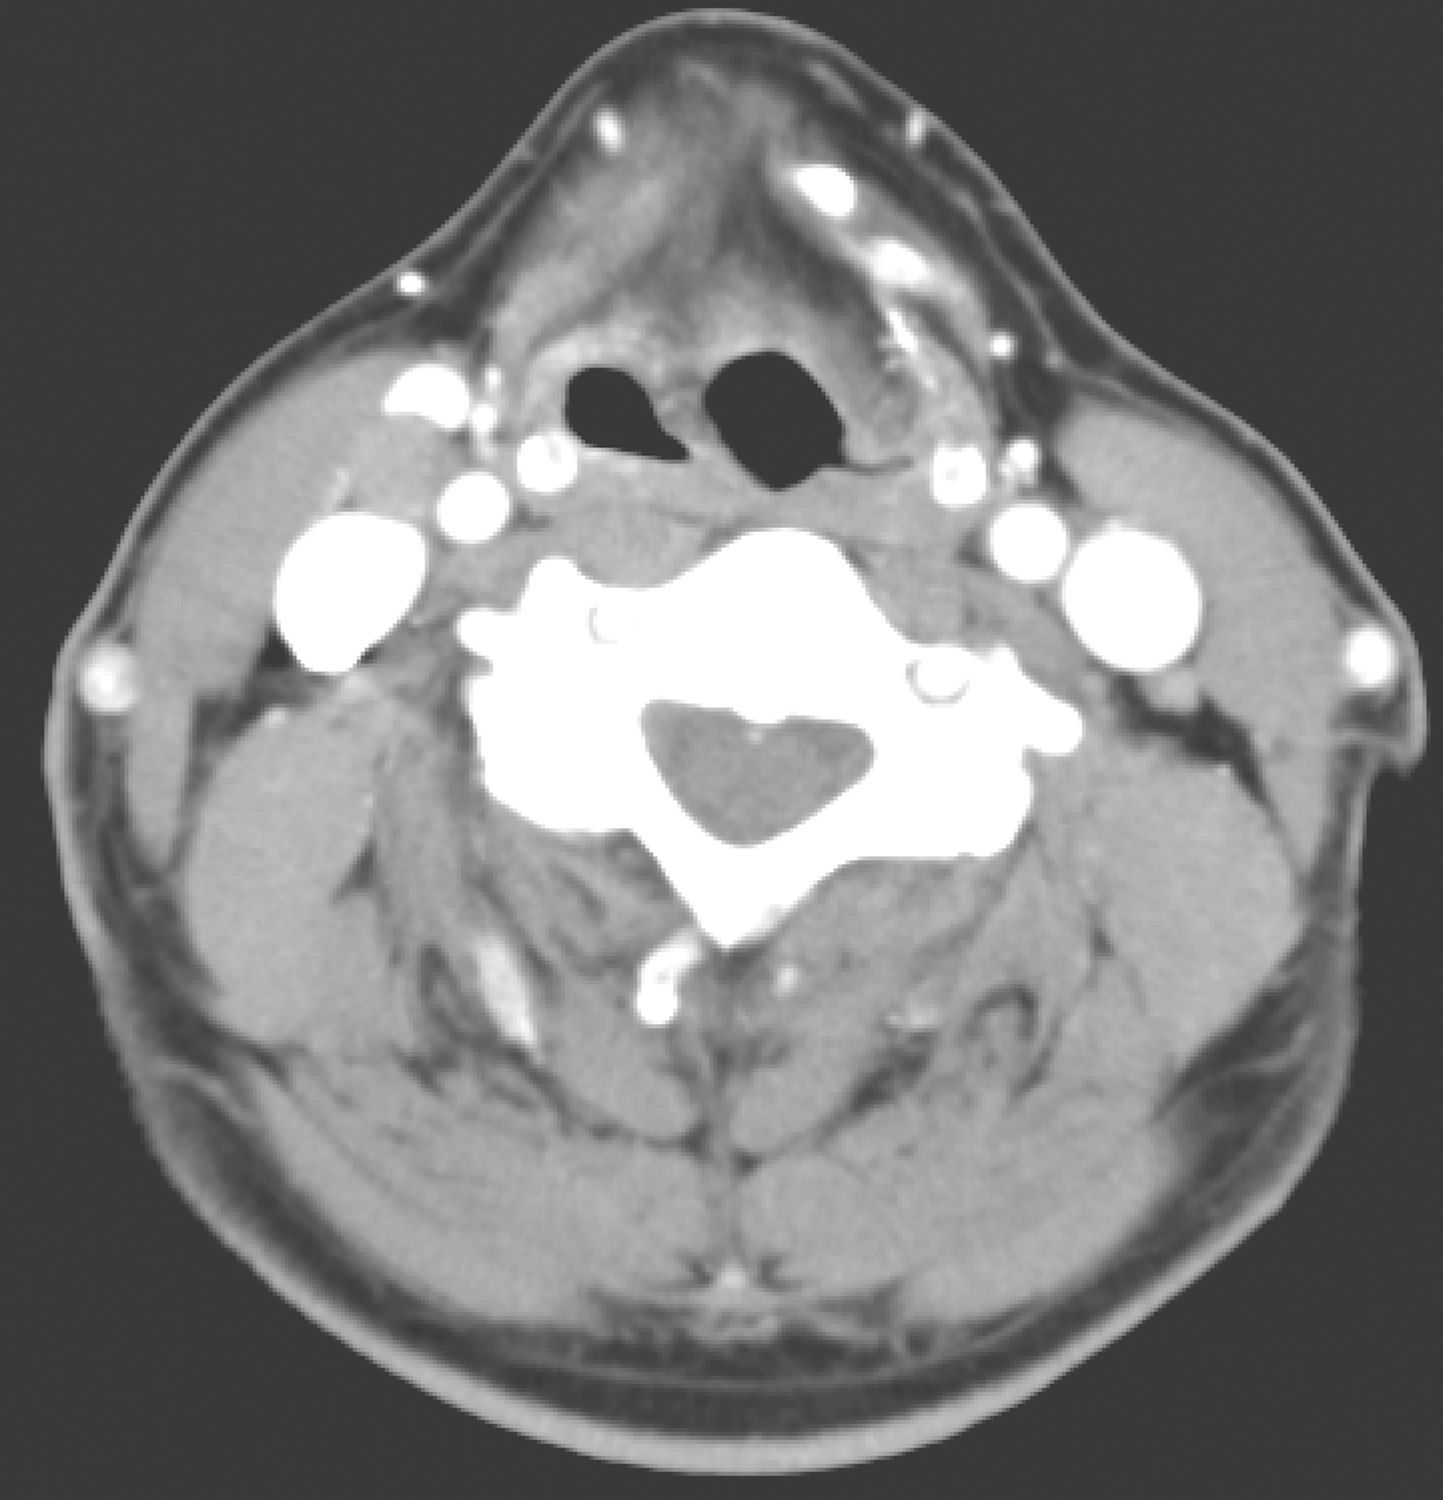

3.2017年3月17日喉MRI

检查所见:右侧室带、声带区可见不规则肿物,最大横截面约3.6cm×1.8cm,T1WI等信号,T2WI/FS中高信号,DWI扩散受限明显,增强扫描呈略不均匀明显强化,病变侵犯右侧喉旁间隙,宽基底贴邻甲状软骨,凸向喉腔,推压对侧声带及室带,喉腔变窄,向前累及前联合(图4)。右侧Ⅱ、Ⅲ区可见多发淋巴结肿大,大者短径约0.9cm(图5)。左颈部Ⅱ区小淋巴结,大者短径约0.5cm。扫描范围内下咽、颌下腺及甲状腺未见明确异常。

图4肿物向前累及前联合

引自:头颈部肿瘤多学科诊疗病例精选.第1版.ISBN:978-7-117-27929-1.主编:李正江

图5右颈部Ⅱ、Ⅲ区可见多发淋巴结

影像学诊断:

(1)右侧室带、声带肿物,符合癌。

(2)右侧Ⅱ、Ⅲ区淋巴结转移可能大;左颈部Ⅱ区小淋巴结,请随诊。